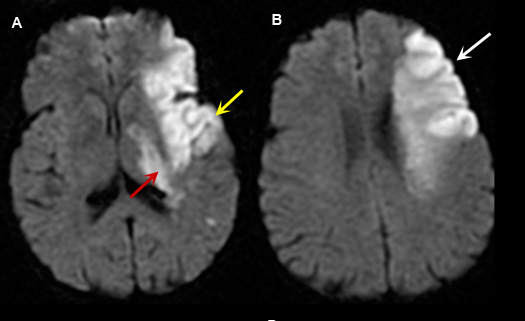

Figure 4: MR Images (DWI)

Left Middle Cerebral Artery Territory Acute Stroke

Case 4:

Imaging findings: Figure 4

- A and B: Diffusion weighted images shows areas of acute infarction as bright signal due to intracellular cytotoxic edema, restricting movement of water molecule in and out of the cell.

- In figure A, left temporal lobe acute infarction (yellow arrow) and left lateral basal ganglia-thalamic regions (red arrow) are noted.

- Left frontal lobe infarct (arrow) is shown in Fig. B.